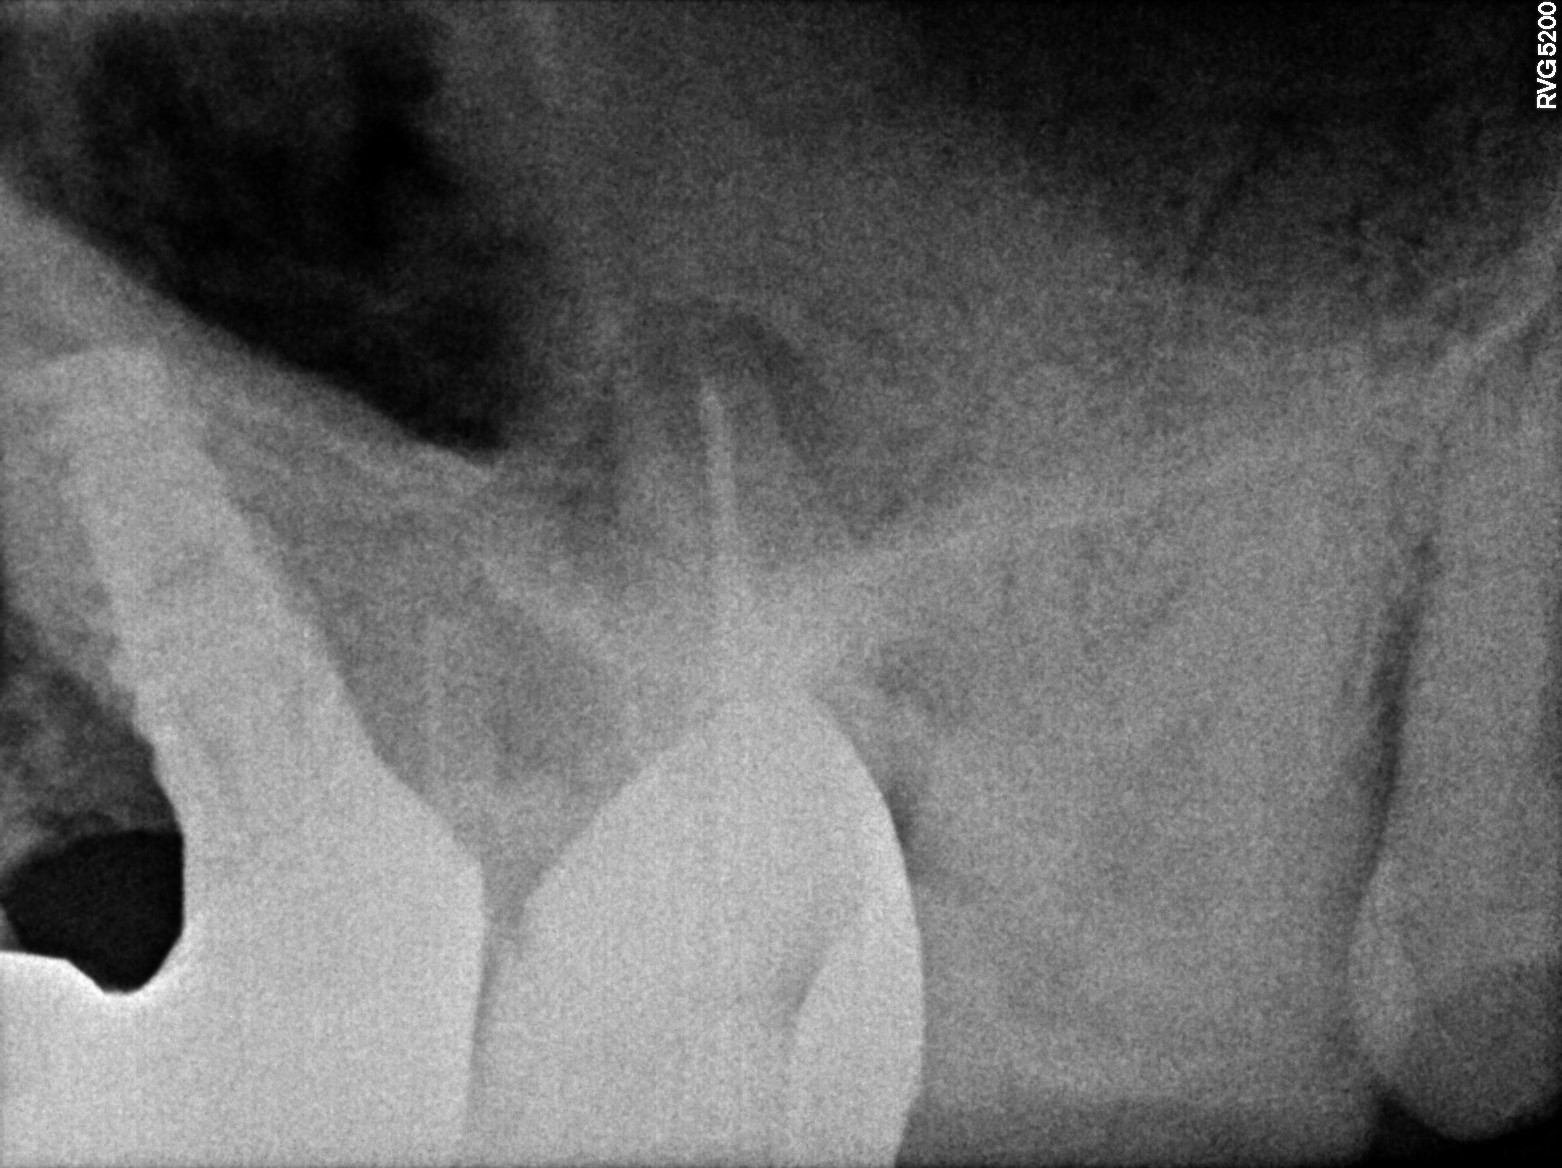

Dental Radiographs FHIR: DocumentReference · LOINC 24641-7

xray_1773475755_1.jpg

24641-7